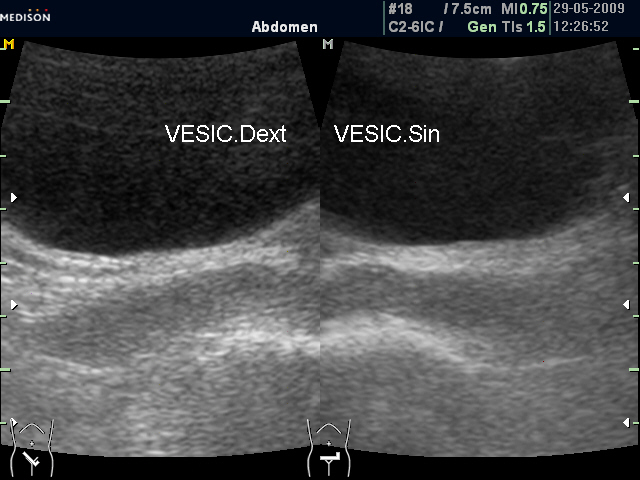

Если участки фиброза в СП при ТА УЗИ видны достаточно редко (см. фото), то выявить асимметрию СП при ТА УЗИ достаточно просто, причем в расширеннм СП, как правило, имеют место застойные явления.

Асимметрия СП (ТА УЗИ)